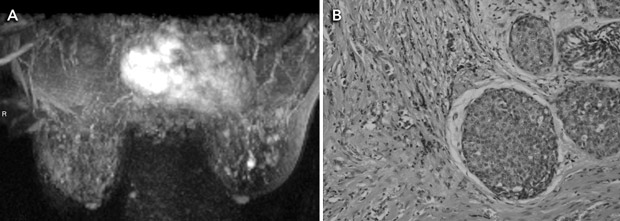

MRI is a highly sensitive test for detecting breast cancer. It is not recommended for screening women at average risk because it is associated with substantial numbers of false-positive results and cost. It has been proposed as adjunct screening for women with a genetic predisposition to breast cancer (Box 3). Mammography has lower sensitivity in this group, detecting fewer than half the breast cancers diagnosed.12

A meta-analysis of five studies of MRI as an adjunct to conventional imaging in high-risk women has provided convincing evidence that MRI detects additional cancers, with an incremental sensitivity of 58% (95% CI, 47%–70%) compared with mammography alone.15-20 Incremental sensitivity was lower when MRI was added to mammography combined with ultrasound examination (44%; 95% CI, 27%–61%) or to mammography combined with ultrasound plus clinical breast examination (range, 31%–33%).15 As summarised in Box 4, the addition of breast MRI led to the earlier detection of eight to 24 additional cancers per 1000 screens.15-20 Differences in MRI yield across studies reflected differences in comparator screening (mammography with or without ultrasound and clinical examination) and variations in disease prevalence. MRI provided the highest cancer yield when used in patients at highest risk.

The effect of detecting MRI-positive (mammogram-negative) cancers on breast cancer mortality, treatment morbidity or the incidence of interval cancers among high-risk (predominantly young) women has not yet been measured. Reductions in breast cancer mortality observed in trials of mammography screening among older, average-risk women have been attributed to the detection of breast cancer at an earlier stage, when the disease is more amenable to treatment. It is not yet clear whether earlier detection of cancers by MRI will bring the same benefits to high-risk women, who may represent a different prognostic group. Accuracy studies comparing tumour size and lymph-node spread between the extra cases detected by MRI and cases detected by conventional imaging alone have not provided consistent evidence that MRI produces a significant stage shift in the detection of breast cancer.15

MRI also increases the likelihood of recall for investigation of false-positive findings, although the evidence is not consistent across studies. Two studies observed that the addition of MRI produces at least a threefold increase in risk of undergoing percutaneous needle biopsy (PNB) for benign findings.17,18 One of these studies also reported a twofold increase in risk of surgical biopsy for benign findings.17 Another study did not find a significant difference in the rate of PNB when MRI was added to mammography, but did not report data on surgical biopsy.16

4 Evidence on magnetic resonance imaging (MRI) as an adjunct to mammography (with or without ultrasonography) in screening young women at high risk of breast cancer

We thank Dr Ruth M L Warren (Department of Radiology, University of Cambridge, United Kingdom) for the MRI images.